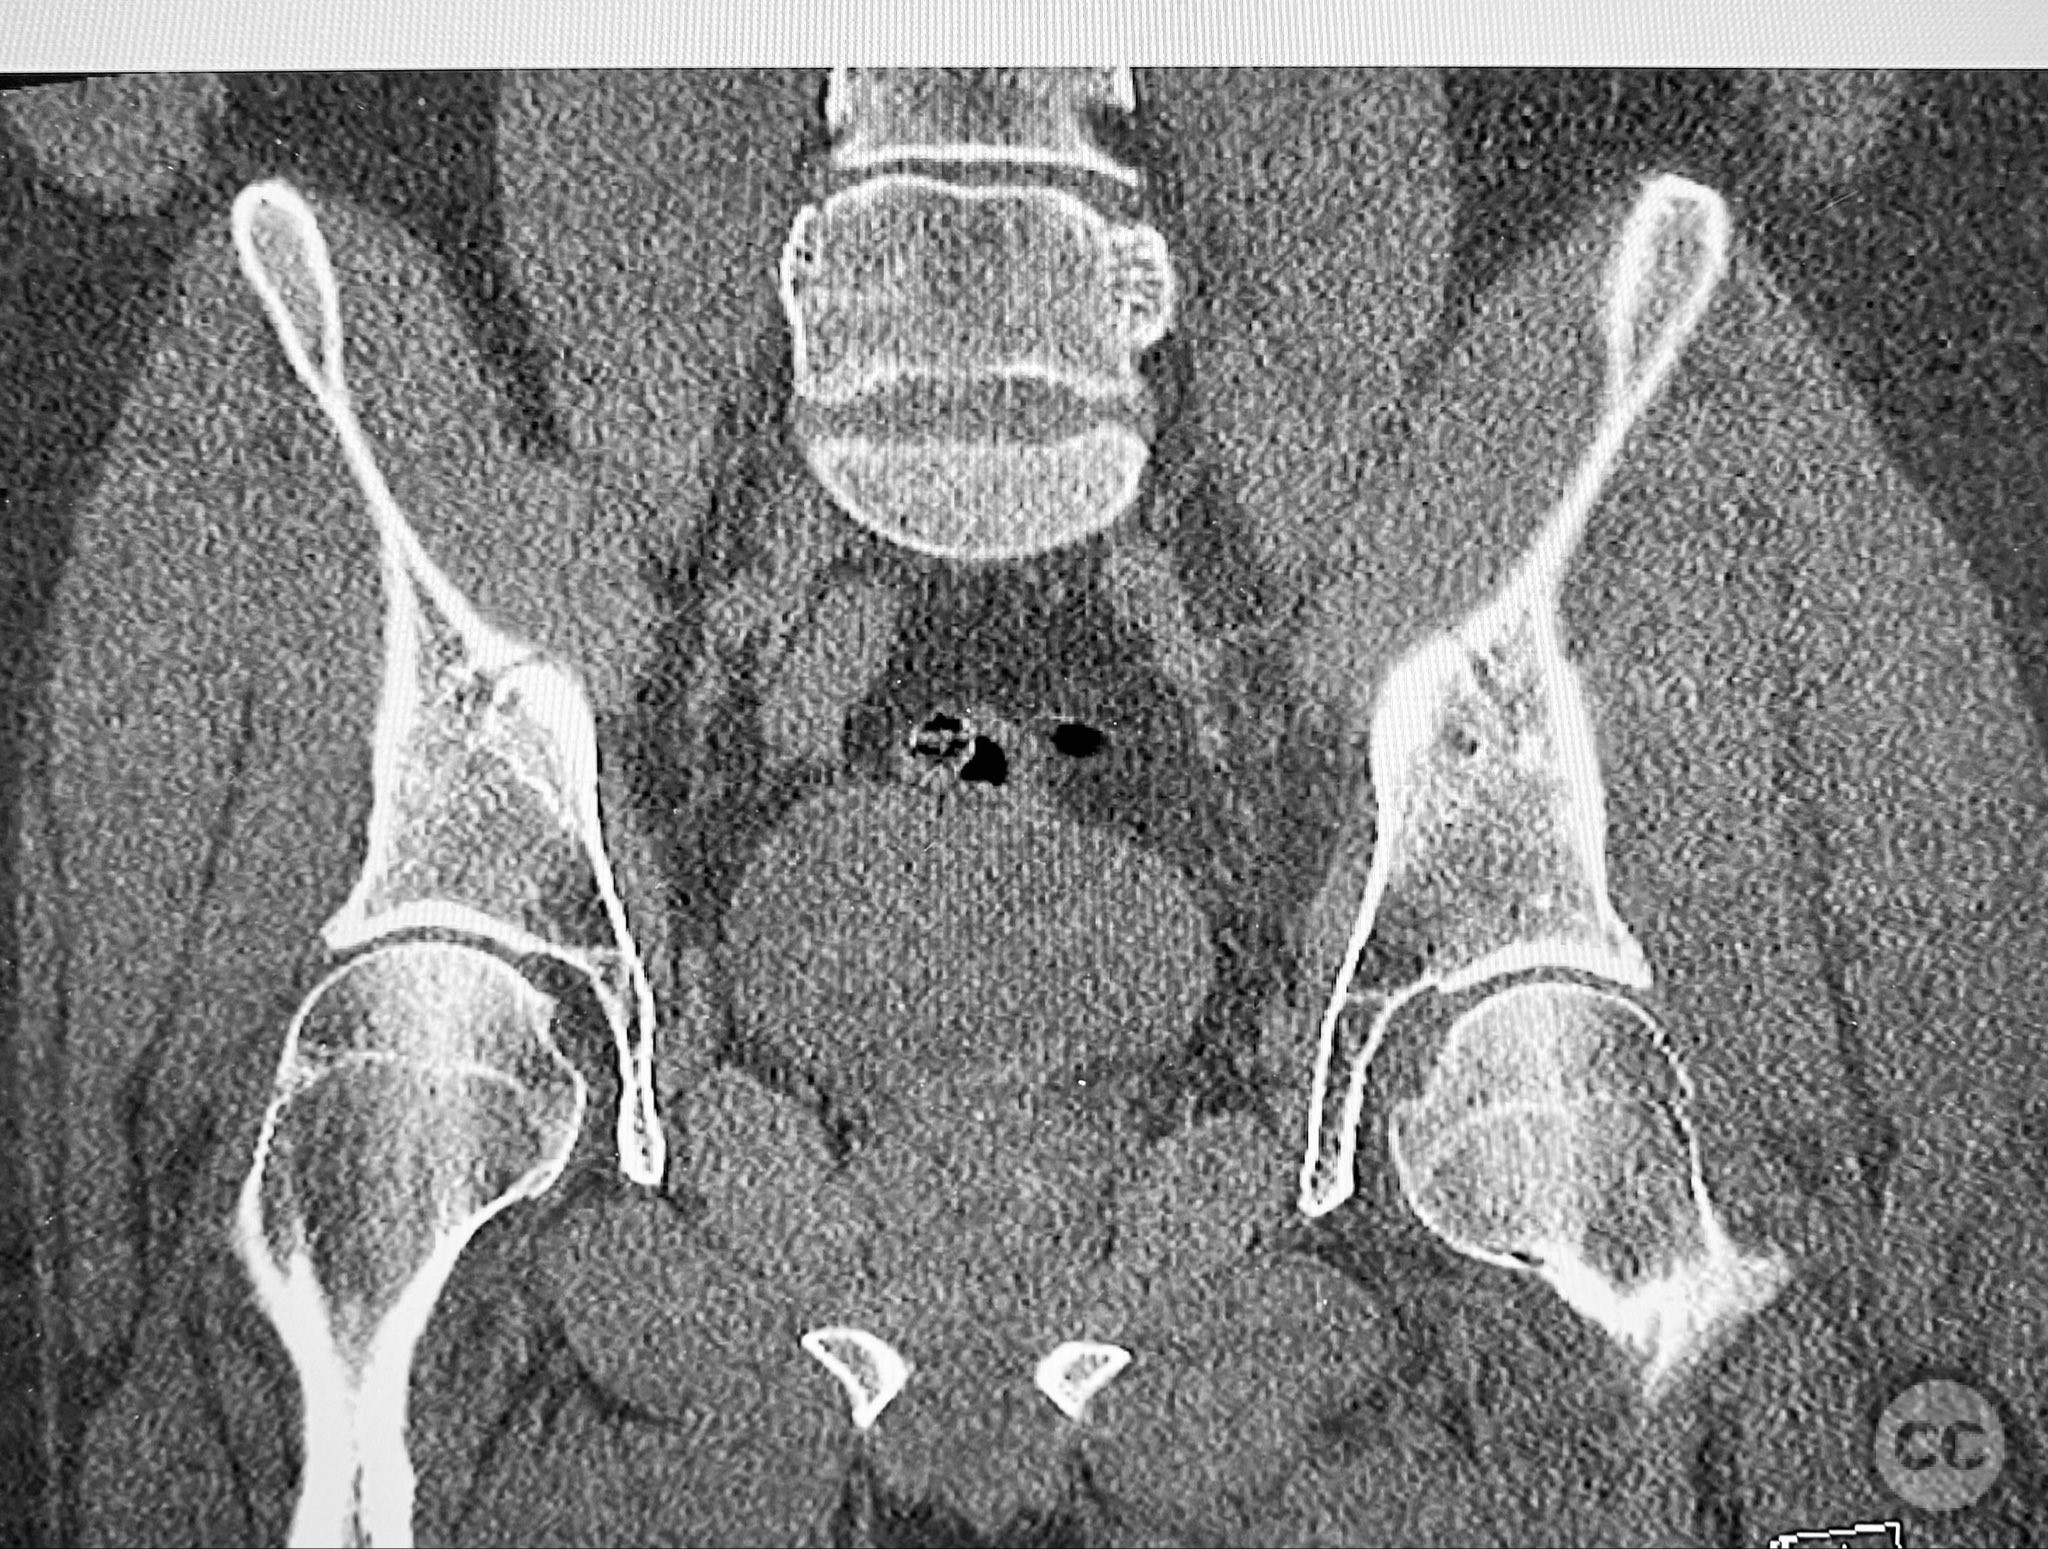

Clinical and radiological findings:  A patient involved in a motor vehicle collision presented with left hip pain exacerbated by any attempted movement. Initial axial and surface-rendered computed tomography (CT) imaging demonstrated an essentially nondisplaced posterior wall (PW) acetabular fracture (AO/OTA 62-A1.1). However, the anteroposterior (AP) scan image and coronal reconstructions revealed significant hip joint asymmetry. Examination under anesthesia with fluoroscopic guidance confirmed persistent joint incongruity, with the femoral head subluxating posteriorly at 50–60 degrees of flexion. A pure chondral fragment was identified as being interposed between the femoral head and the intact region of the posterior wall, accounting for the clinical and radiological asymmetry.